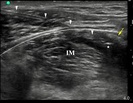

Wobec doświadczeń dotyczących anestezji przewodowej przez igłę, cewniki zakładane pod kontrolą ultrasonografii z dostępu podobojczykowego przedstawiane są jako zapewniające lepszą analgezję, niż te zakładane z dostępu nadobojczykowego. Technika podawania bolusa przez cewnik, która niewątpliwie „sprawdza” skuteczność cewnika przed rozpoczęciem ciągłej infuzji została zbadana dla cewników zakładanych z dostępu podobojczykowego, ale nie dla dostępu nadobojczykowego. Poniższe badanie ocenia technikę podawania bolusów przez cewnik zakładany z dostępu nadobojczykowego i weryfikuje hipotezę, iż cewnik zakładany z dostępu podobojczykowego zapewnia szybszy początek wystąpienia blokady splotu barkowego.

więcejPorównanie skuteczności cewników okołonerwowych zakładanych z dostępu pod i nadobojczykowego celem anestezji przewodowej w powtarzanych bolusach przez pozostawiony cewnik.